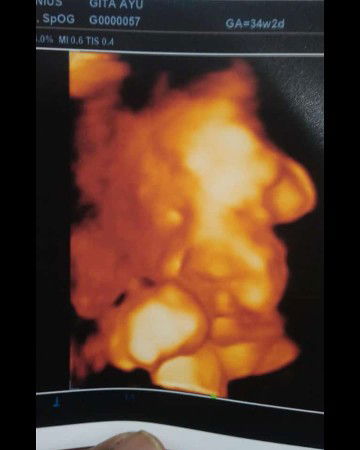

34week 2day sudah masuk panggul

sharing aja ya bun,, kmrn habis USG 4D nih bun baby nya udh masuk panggul dan bbj 2.5kg pdhl di usia 32 week itu bbj nya 1.9kg di 34 week lngs aja naik jd 2.5kg😂😂😂 alhmdllh ya bun , smua prsiapan kelahiran dan perlengkapan bayi pun sdh lengkap tinggal menunggu wktnya launcing aja nih .. dan sekarang sdh mulai sering Kontraksi palsu pinggang sakit, kram ,mules tp blm ada tanda tanda keluar lendir kata dokter msh aman . hmya kontraksi palsu... ada kah yang samaa sprti saya bun mglami kontraksi palsu di 34w ??? sempet worry sih bun krna ini anak pertama ,saat kontraksipun juga rasanya nano² ya bun😂😂 menunggu Hpl akhir juni nih .. jd gak sabar an pgn cpt ktm dedek nya... paas di usg smua grafiknya bagus alhdmllh .. smoga smuanya dilancarkan ya bun tanpa ada trauma2 mendalam😂😂😂🤟#firstbaby #jangandibully #ingintahu #bantusharing #BabyBoy